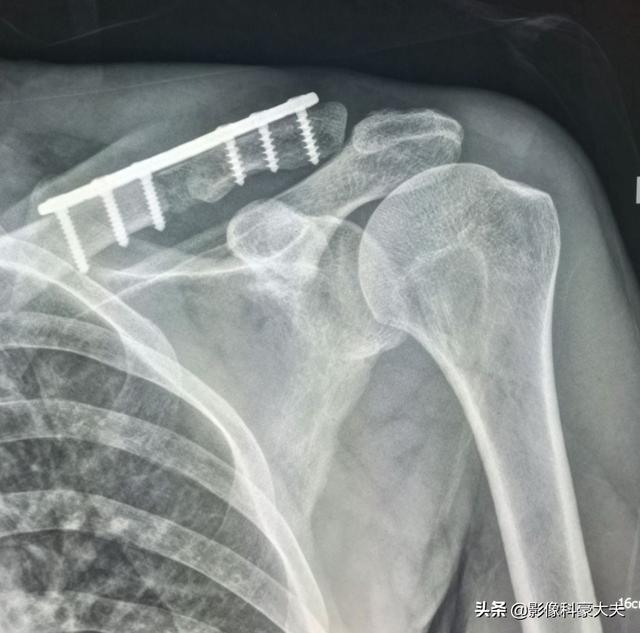

5年間生存している低分化癌の鎖骨転移

この症例は58歳のゲイ男性で、肩を軽く伸ばしただけで痛みが続くようになり、X線検査で低密度病巣が見つかった:

これは骨転移に基づく軽微な外力による病的骨折であった。穿刺が行われ、病理結果は低分化肺腺癌の骨転移であった。

これは、当時彼が鎖骨骨折のために受けた内固定手術で、手術をしなければ自然治癒が非常に難しい病的骨折である。